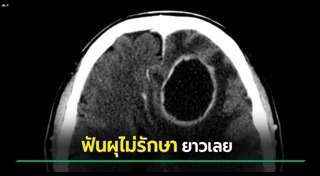

รวมเรื่องเกี่ยวกับระบบสมองที่เราอาจจะยังไม่รู้ ระบบการทำงานด้านต่าง ๆ พร้อมภาพประกอบ